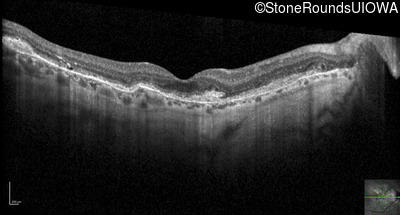

Optical Coherence Tomography - Right - 20/25 +1

Exemplar / OCT Stack

OCT Stack